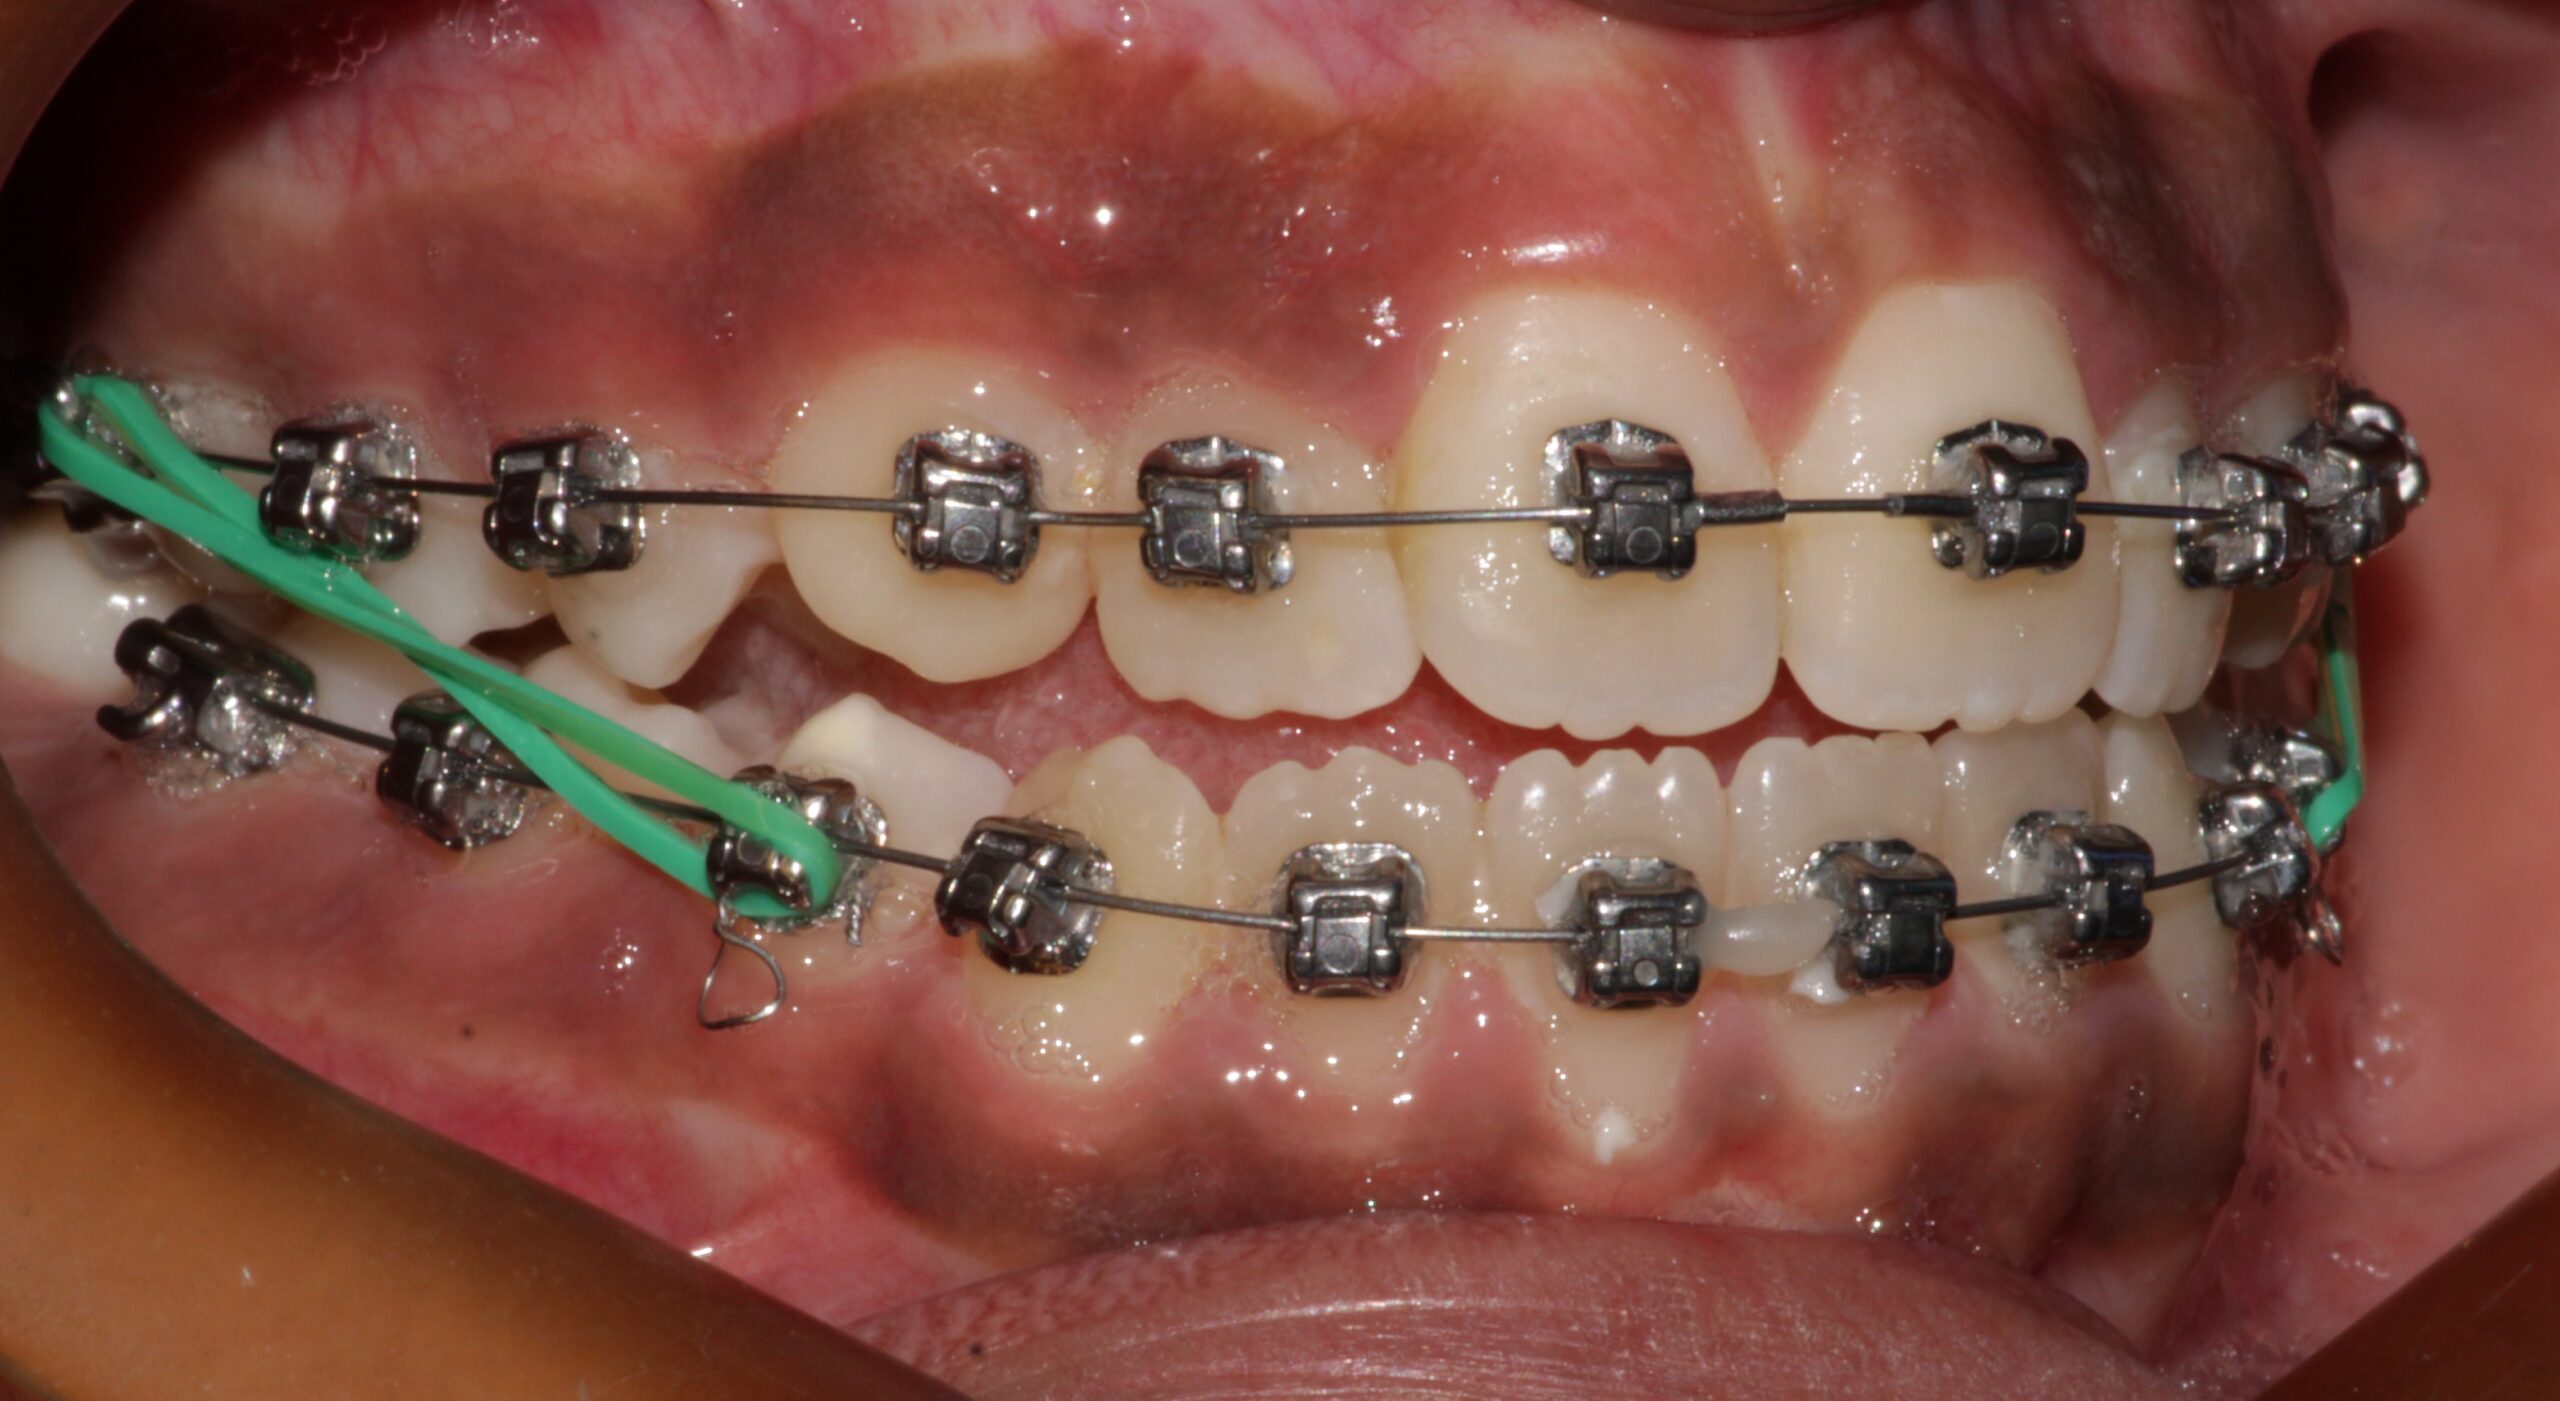

During The Treatment

During The Treatment